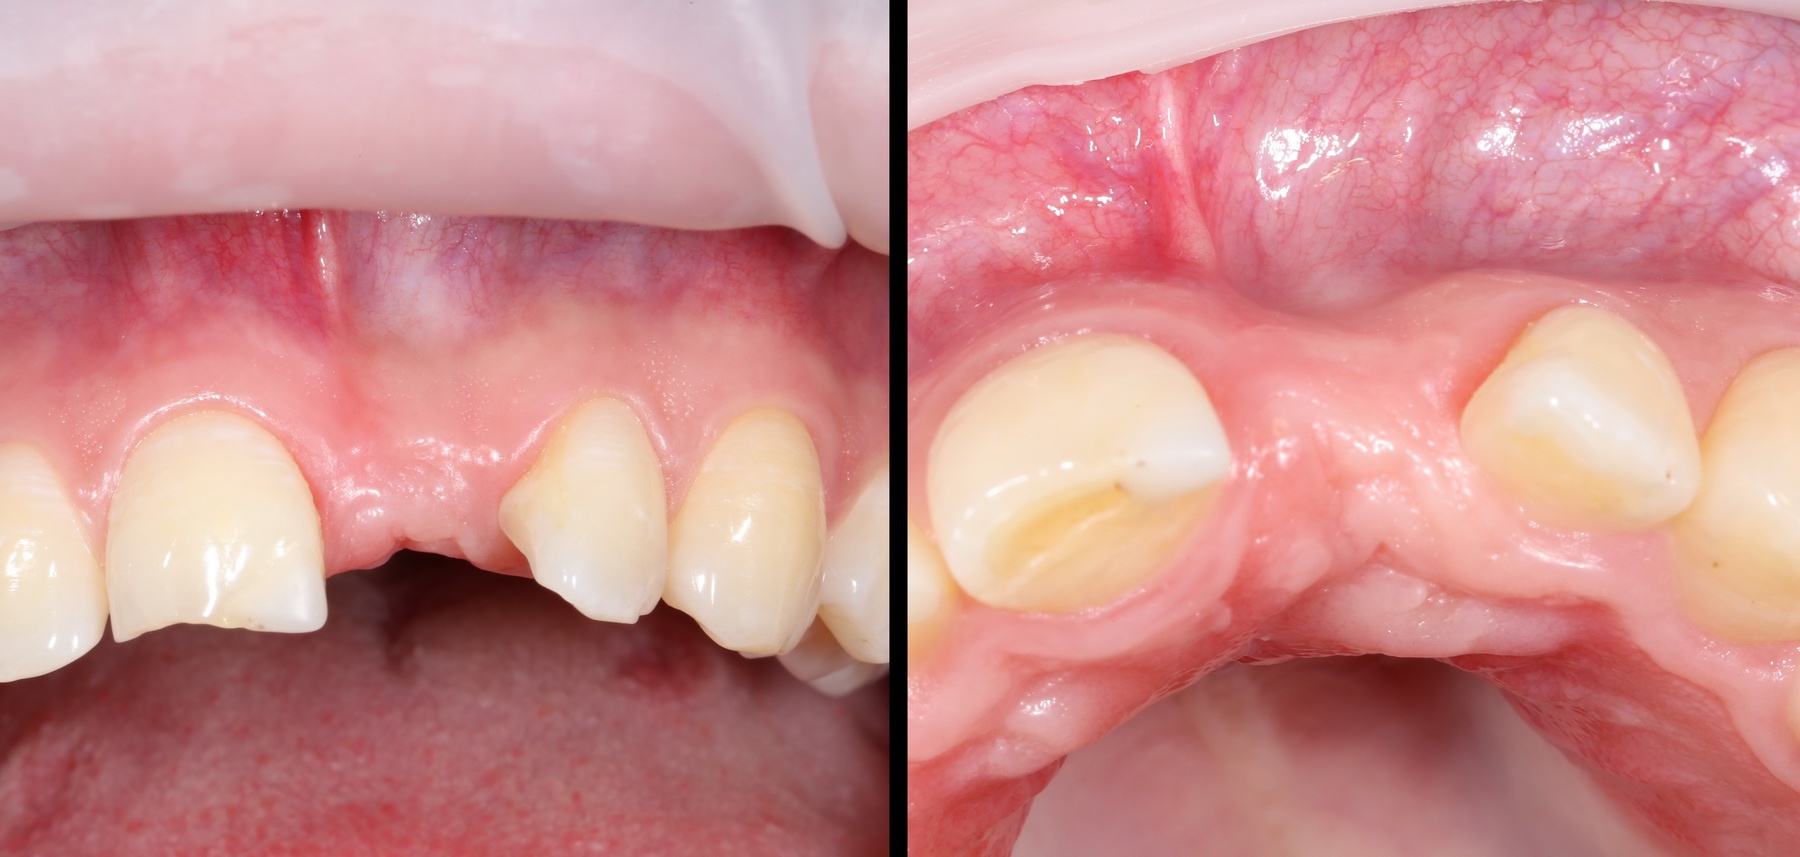

A09A4427 (2) IMG_8420 (2)

в частности, для верхних премоляров существует правило, по которому ось импланта должна проходить через фиссуру или, в крайнем случае, щечный бугор зуба (см. фотографии выше).